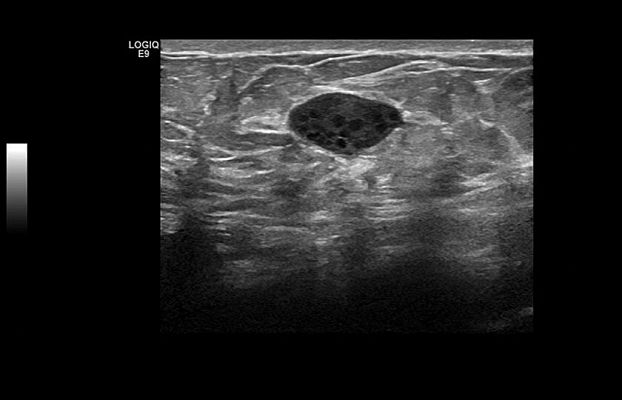

Клинические изображения

LOGIQ E9 XDclear 2.0 — это непревзойденные возможности диагностики при проведении ультразвуковых исследований у пациентов любой комплекции и возраста. Система позволит получить достоверные результаты как при сканировании технически сложных пациентов с избыточным весом, так и для новорожденных с небольшой массой тела.

В новой версии системы были модернизированы практически все элементы, отвечающие за процесс формирования изображений — от сигнальных последовательностей датчиков до алгоритма повышения четкости на уровне отдельных пикселей, в результате платформа XDclear 2.0 позволяет получить более высокое разрешение одновременно с увеличенной глубиной проникновения.

LOGIQ E9 XDclear 2.0 — это непревзойденные возможности диагностики при проведении ультразвуковых исследований у пациентов любой комплекции и возраста. Система позволит получить достоверные результаты и при сканировании технически сложных пациентов с избыточным весом, и для новорожденных с небольшой массой тела.

В новой версии системы были модернизированы практически все элементы, отвечающие за процесс формирования изображений — от сигнальных последовательностей датчиков до алгоритма повышения четкости на уровне отдельных пикселей, в результате платформа XDclear 2.0 позволяет получить более высокое разрешение одновременно с увеличенной глубиной проникновения.

- Существенное повышение контрастности более чем на 20% даёт возможность различать даже самые небольшие детали на изображении.

- Вдвое увеличенное пространственное разрешение позволяет производить идеальную фокусировку.